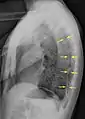

الأشعة السينية على الصدر

عادة ما يكون التصوير الشعاعي العادي للصدر، بإشعاع الأشعة السينية من الخلف (من الخلف للأمام) هو أنسب فحص في البداية. وعادة ما يتم تنفيذ ذلك خلال الشهيق (مع كتم النَفَس). لأن التصوير بالأشعة السينية أثناء الزفير (بعد خروج الهواء) لا يعطي أي معلومات إضافية.[12][13] إذا لم تُظهر الأشعة السينية الساقطة من الخلف للأمام استرواح صدري، ولكن كان هناك شكوك قوية في وجوده، يتم عمل أشعة سينية جانبية ( بإسقاط الأشعة من الجانب)، ولكن هذه ليست الطريقة الروتينية.[13][17] ومن المألوف وجود انحراف المنصف (التركيب بين الرئتين التي يحتوي على القلب، والأوعية الدموية الكبيرة، والممرات الهوائية الكبيرة) بعيدا عن الرئة المتضررة بسبب اختلافات الضغط. لذا فإن هذا الانحراف ليس دليلا على حدوث استرواح الصدر الضاغط، إنما يتحدد أساسا عن طريق مجموعة من الأعراض بالإضافة إلى نقص الأكسجين، والصدمة.[12]

الأشعة المقطعية

التصوير المقطعي بالكمبيوتر ليس ضروريا لتشخيص استرواح الصدر، ولكن يمكن أن يكون مفيدا في حالات معينة. في بعض أمراض الرئة، وخاصة انتفاخ الرئة، يمكن أن يوجد مناطق من الرئة غير طبيعية مثل وجود فقاعات (كيس كبير مملوء بالهواء) يكون لها نفس مظهر استرواح الصدر بالأشعة السينية على الصدر، وقد لا يكون آمنا تطبيق أي علاج قبل القيام بالتمييز، وتحديد الموقع الدقيق، وحجم استرواح الصدر.[13] في حالة الخبطات أو الطعنات، قد لا يكون من الممكن إجراء فيلم في الوضع القائم، وقد لا يتمكن التصوير الشعاعي للصدر من تصوير ما يصل إلى ثلث استرواح الصدر، لذا يكون التصوير المقطعي بالكمبيوتر هو الأفضل في هذه الحالة.[16]

وهناك استخدام آخر للأشعة المقطعية هو في تحديد أي أمراض أخرى كامنة في الرئتين. حيث يمكن أن يساعد على تحديد البثور أو الأمراض الكيسية (تحسبا للعلاج، انظر أدناه) في حالة استرواح الصدر الأولي، كما يمكن أن يساعد على تحديد معظم الأسباب المذكورة أعلاه في حالة استرواح الصدر الثانوي.[13][17]